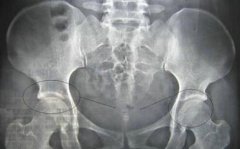

来院后,由风湿专病科室王怀庆主任接诊,随即为王先生进行了详细的检查:血沉109mm/h,类风湿因子(-)C反应蛋白<10,HLA-B27(+);IgG10.2g/L,IgA0.93g/L,IgM2.37g/L ,抗ENA抗体谱阴性。...[详细]